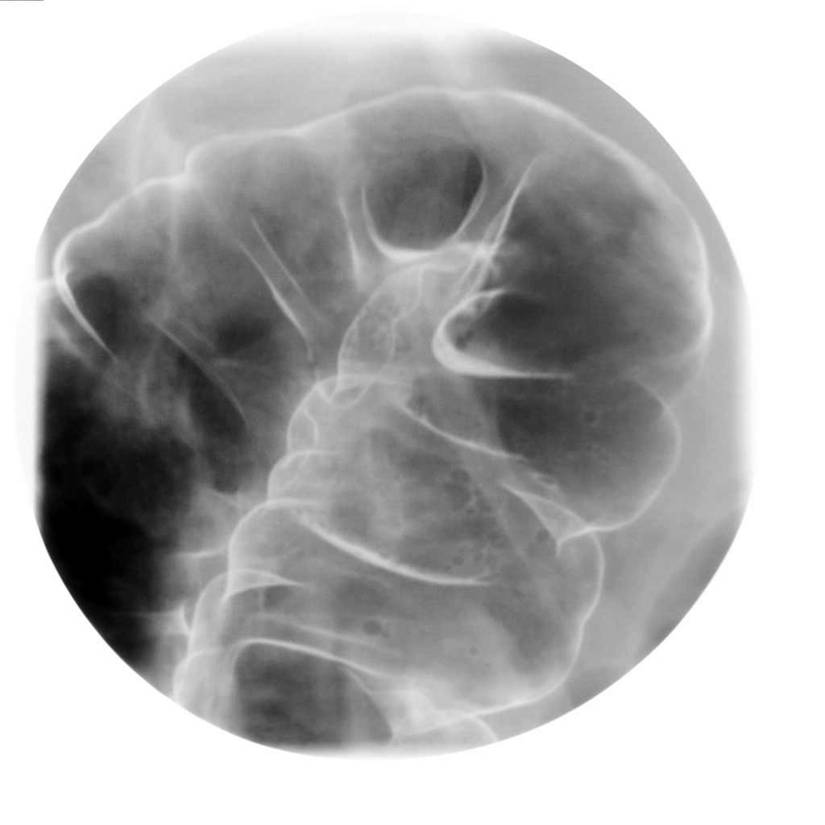

大腸攝影檢查

| 主要檢查大腸有無解剖異常、通過障礙、潰瘍、腫瘤、憩室、息肉等所有大腸內或外之病灶。病患若有血便、慢性腹痛、腹瀉或排便習慣改變、體重減輕等徵兆,皆可藉此檢查作更進一步的治療評估。 | ||||||||||||